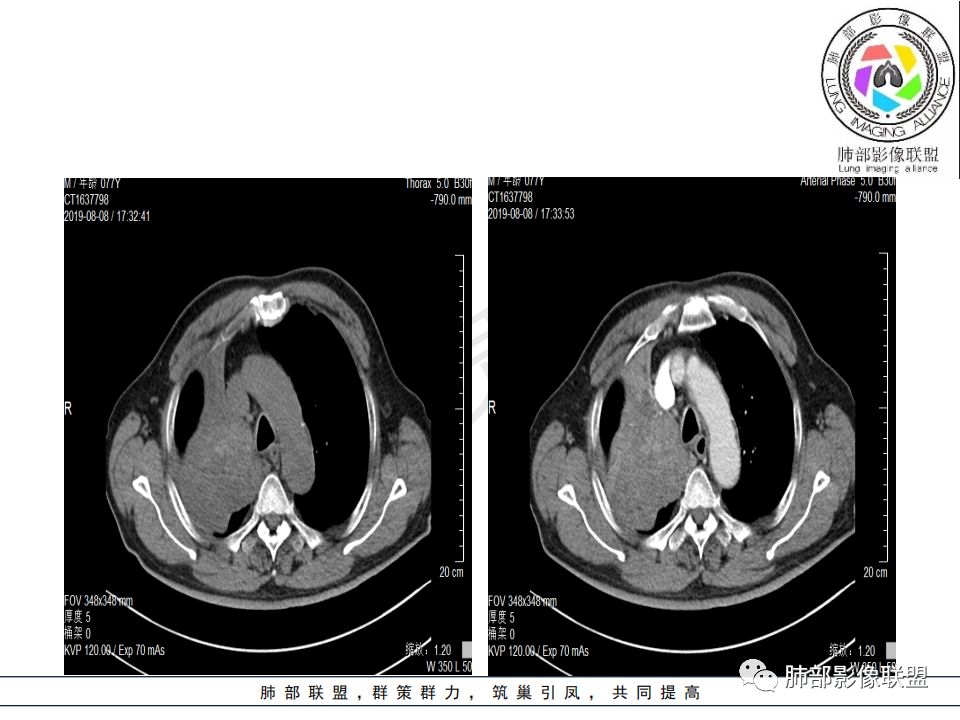

病史:男.77岁,咳嗽1月;干咳,少许白痰,无发热,2013胃癌术后,角蛋白24.65(0-3.07),SCC和proGRP不高;

影像:影像右侧大支气管阻塞,临床没有症状或很轻微,要想到胃腺癌转移;胸壁代偿好,透亮度稍低不明显,慢性过程;34.8-52.5HU,主病灶支气管前壁另有1结节,都做成增强两期了,动脉期较平扫有强化;

诊断:多发,转移,无淋巴结及胸腔积液;

鉴别:原发鳞癌。

晨读:患者老年男性,以咳嗽一月就诊,少量白痰,胸CT:纵隔右移,右肺体积缩小,气管下段管壁可见结节样改变,气管软骨变形,气管下段及右主支气管可见新生物向管壁浸润,并向管腔外生长,右上肺肺不张,但不张边缘可见病灶呈膨胀性生长,可见分叶,增强后强化明显。考虑:肺部恶性病变(鳞癌?)